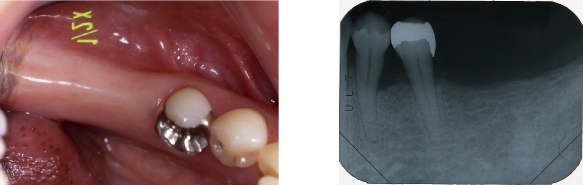

インプラント症例③ ~ほとんど歯が無い例~

●残っている歯が2本しかなく、上下、入れ歯を何度と作っているが、全然合わない。

●上にはインプラントを6本入れて、固定式の歯を入れました。

●下にはインプラントを4本入れて、マグネットを取り付けて、安定する入れ歯にしました。

※インプラントにするには、支えとなる骨が必要です。

場合によっては、事前に骨を作る処置を行います。